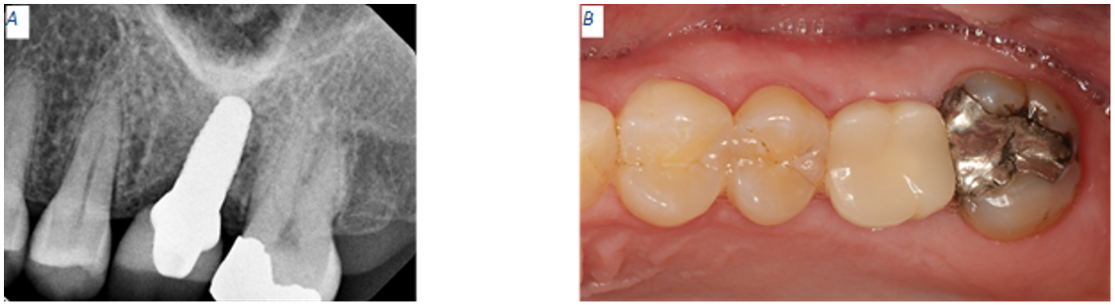

After two weeks of healing, our patient presented for post-operation follow-up. During this appointment, we obtained a new periapical radiograph for site #14 and performed a clinical evaluation. The patient didn’t have any concerns, and she didn’t report any complications. Clinically and radiographically, everything was healing within normal limits and sutures remained intact. The tissues surrounding site #14 and tooth #18 were superficially debrided with a cotton tip applicator saturated with 0.12% chlorhexidine gluconate and the remaining gut sutures were removed. The patient received a post-operation brush to restart mechanical oral hygiene on and around the surgical sites (Fig 4).

Six months post implant placement

At the six months appointment, the PEEK healing abutment was removed from the osseointegrated implant as site #14. A NobelPearl Straight Engaging Inter-X Prefabricated Zirconia Abutment was tried and torque to only 15 N·cm to allow for occlusal reduction until enough space was available for the final restoration. After abutment modification, the abutment was torqued to 25 N·cm using the Vicarbo NobelPearl Definitive Clinical Screw Inter-X (carbon-fiber reinforced PEEK). The access screw channel was obturated using Polytetrafluoroethylene (PTFE) tape. An IPS e.max crown was fabricated using the integrated CEREC Dental CAD/CAM System. The e.max crown was cemented using Rely-X Luting (resin modified glass ionomer cement). Excess luting cement was removed, and a verification periapical radiograph was obtained (Fig 5). Twelve days after the implant supported, cement retained restoration for site #14 was delivered, a flat plane, full arch, hard night guard was delivered to decrease the chances of biomechanical overloading due to excessive and unintentional occlusal force on the implant restoration.

Figure 4: Two weeks post operation. (A) PEEK abutment not visible in periapical radiograph. Implant appears to have a distal tilt. (B) Site #14 displays soft tissue healing within normal limits.

Figure 5: Two weeks post operation. (A) PEEK abutment not visible in periapical radiograph. Implant appears to have a distal tilt. (B) Site #14 displays soft tissue healing within normal limits